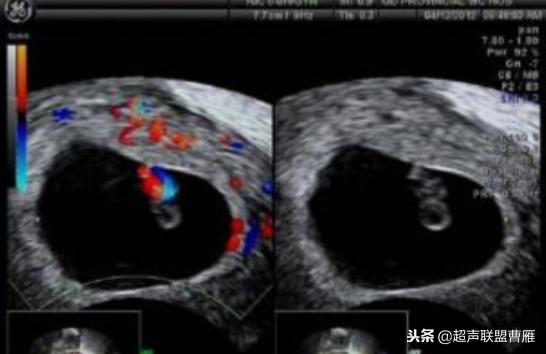

妊娠40天,见到卵黄囊、胚极及心管搏动, HCG12800U/L。

妊娠35天,高分辨的超声检查就可能见到心管搏动、胚极及卵黄囊。

胎芽 卵黄囊 心管搏动信号